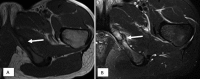

Figure 8.

15-year-old female cross country runner with pubic pain, referred for MRI to “rule out sports hernia.” (A) Axial T1 and (B) T2FS images demonstrate a healing fracture (arrows) through the left inferior pubic ramus. This was radiographically occult.

Figure 9.

13-year-old baseball player (shortstop) with gradually worsening groin pain. (A) Axial T1 and (B) axial T2FS images demonstrate bone marrow edema at the left ischial tuberosity (arrows). The hamstring tendons appeared normal. (C) Retrospective review of the radiograph shows subtle cortical irregularity along the lateral aspect of the left ischium (arrow).